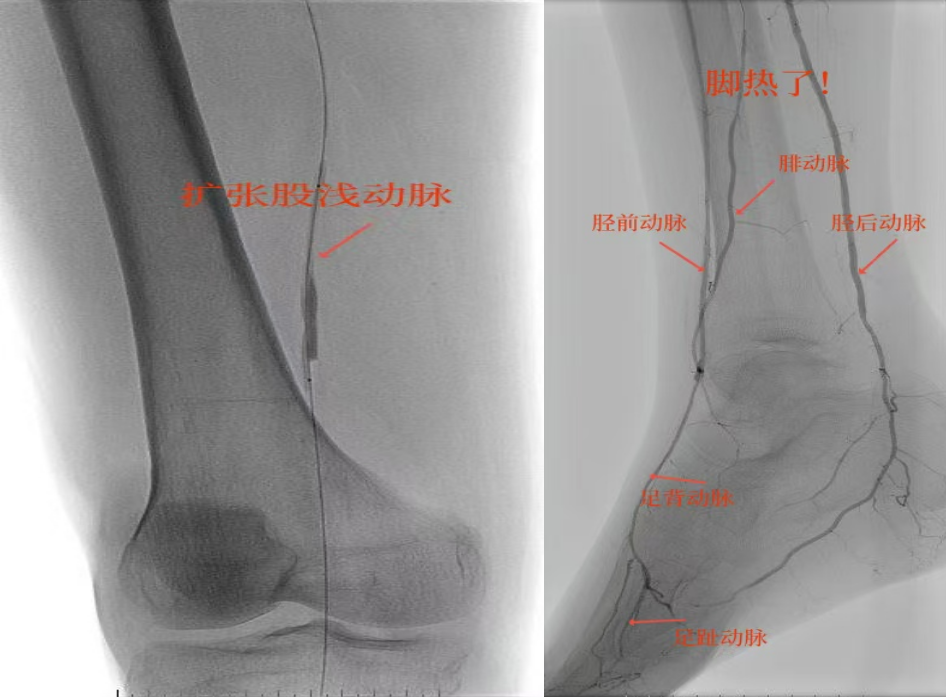

67岁女性患者,多年糖尿病、冠心病史,因右足溃烂伴凉麻疼痛长达2年就诊,此前曾接受外院介入术后血管再度闭塞。此次检查发现其股浅动脉、腘动脉至膝下血管全程闭塞,且伴有严重钙化。团队迎难而上,创新性经足背动脉逆向穿刺,耗时3小时成功贯通胫前动脉。术后当夜患者足部即感回暖,溃烂足趾疼痛显著缓解。术后结合中药外治(换药、熏洗、去腐生肌膏外敷)加速创面愈合。该患者已于出院,院外换药治疗。

影像检查:股浅动脉、腘动脉至膝下血管全程闭塞伴严重钙化。